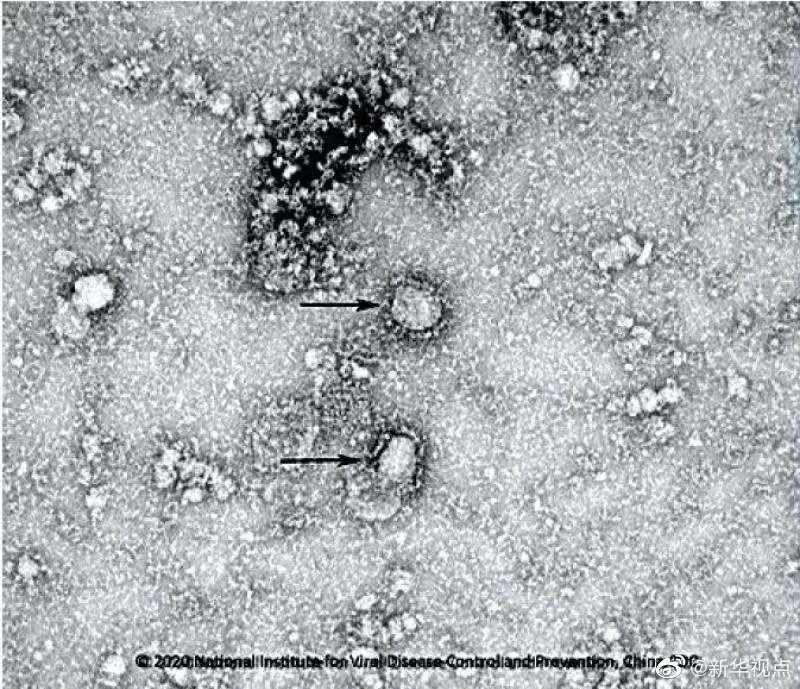

國(guó)家病原微生物資源庫(kù)于2020年1月24日發(fā)布了由中國(guó)疾病預(yù)防控制中心病毒病預(yù)防控制所成功分離的我國(guó)第一株病毒毒種信息及其電鏡照片、新型冠狀病毒核酸檢測(cè)引物和探針序列等國(guó)內(nèi)首次發(fā)布的重要權(quán)威信息,并提供共享服務(wù)。看病毒“真容”↓↓↓(記者田曉航、王秉陽(yáng))

好消息!中國(guó)疾控中心成功分離我國(guó)首株新型冠狀病毒毒種,它長(zhǎng)這樣!-新華網(wǎng)